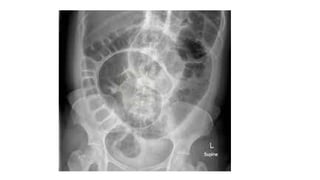

• Abdominal x-ray (coffee bean/sigma sign, fridmandell’s sign,omega

sign)

- Erect x-ray - gases

- Supine x-ray - gas fluid levels